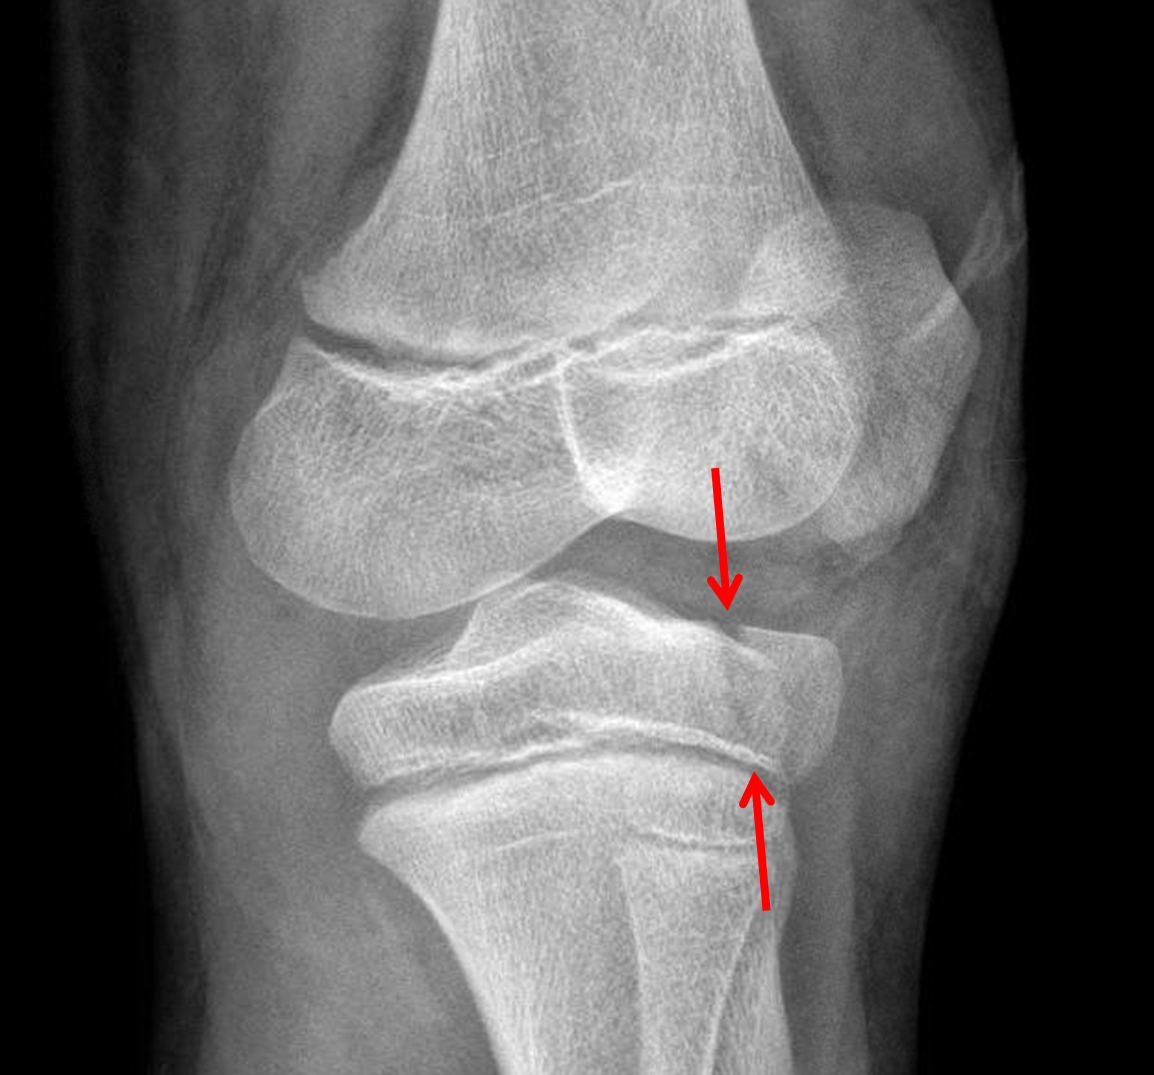

Age: 11

Sex: Male

Indication: Knee pain

Sample ReportAcute nondisplaced, nondepressed fracture of the lateral tibial plateau with extension into the physis (Salter III). Surrounding soft tissue swelling.

Large joint effusion.

No joint malalignment.